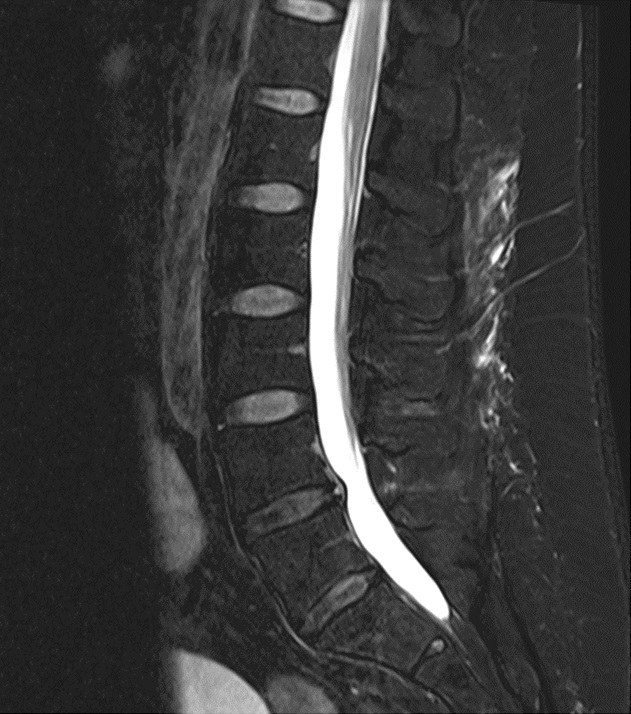

We are currently performing studies on the role of facet joint osteoarthritis in chronic back pain and spinal stenosis in our laboratory. One of our focuses are neurogenic inflammation and ectopic calcification in facet joints as potential therapeutic target.